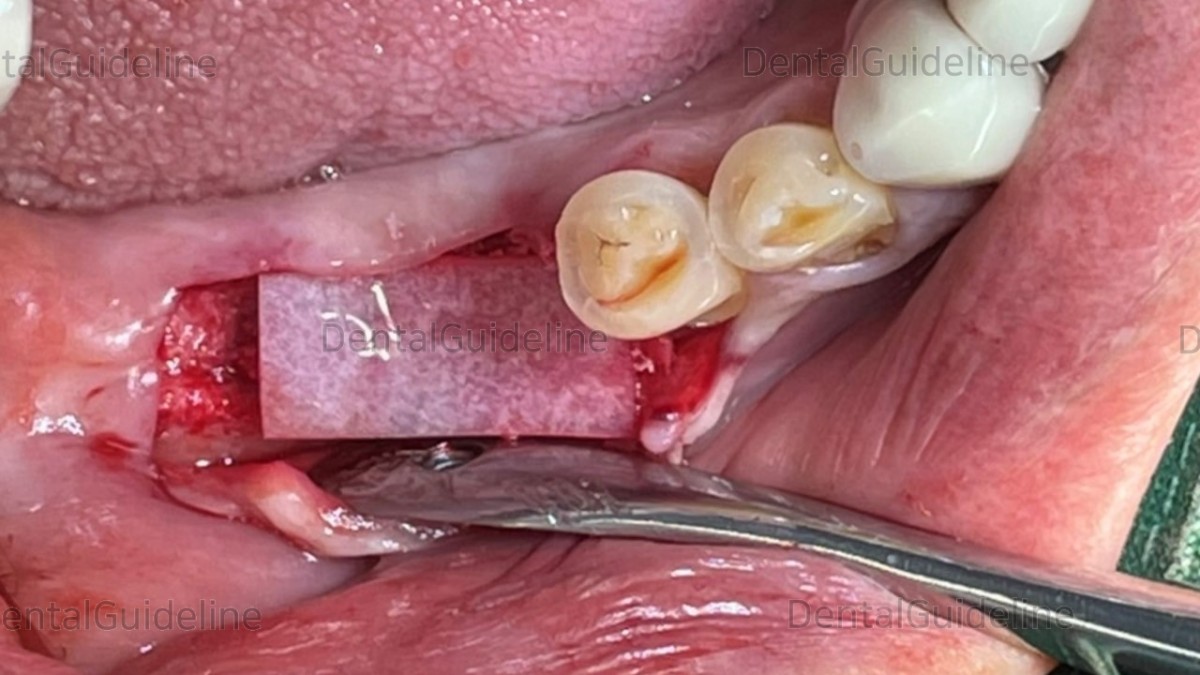

Additive GBR was performed.

collagen membrane

The flap was closed.